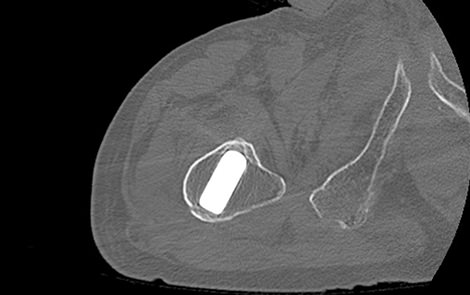

16列マルチスライスCT装置 Aquilion Lightning(キャノンメディカルシステムズ製)を導入しており骨折の診断、手術前計画目的の撮影、骨癒合経過観察目的で検査を行っています。CTでは撮影した元データより様々な断面の画像を再構成(MPR画像)でき、骨の外観のような三次元的な画像(VR画像)も作成でき、レントゲンでは評価しづらい細かい骨折の診断などにも優れています。撮影時間は数分で終わります。